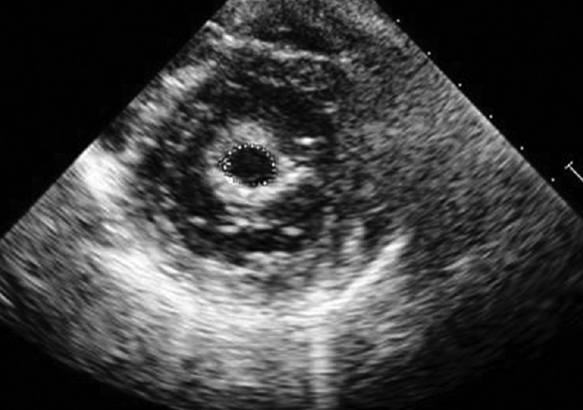

what does a bicuspid valve look like in PSAX?

in systole only 2 leaflets “open”